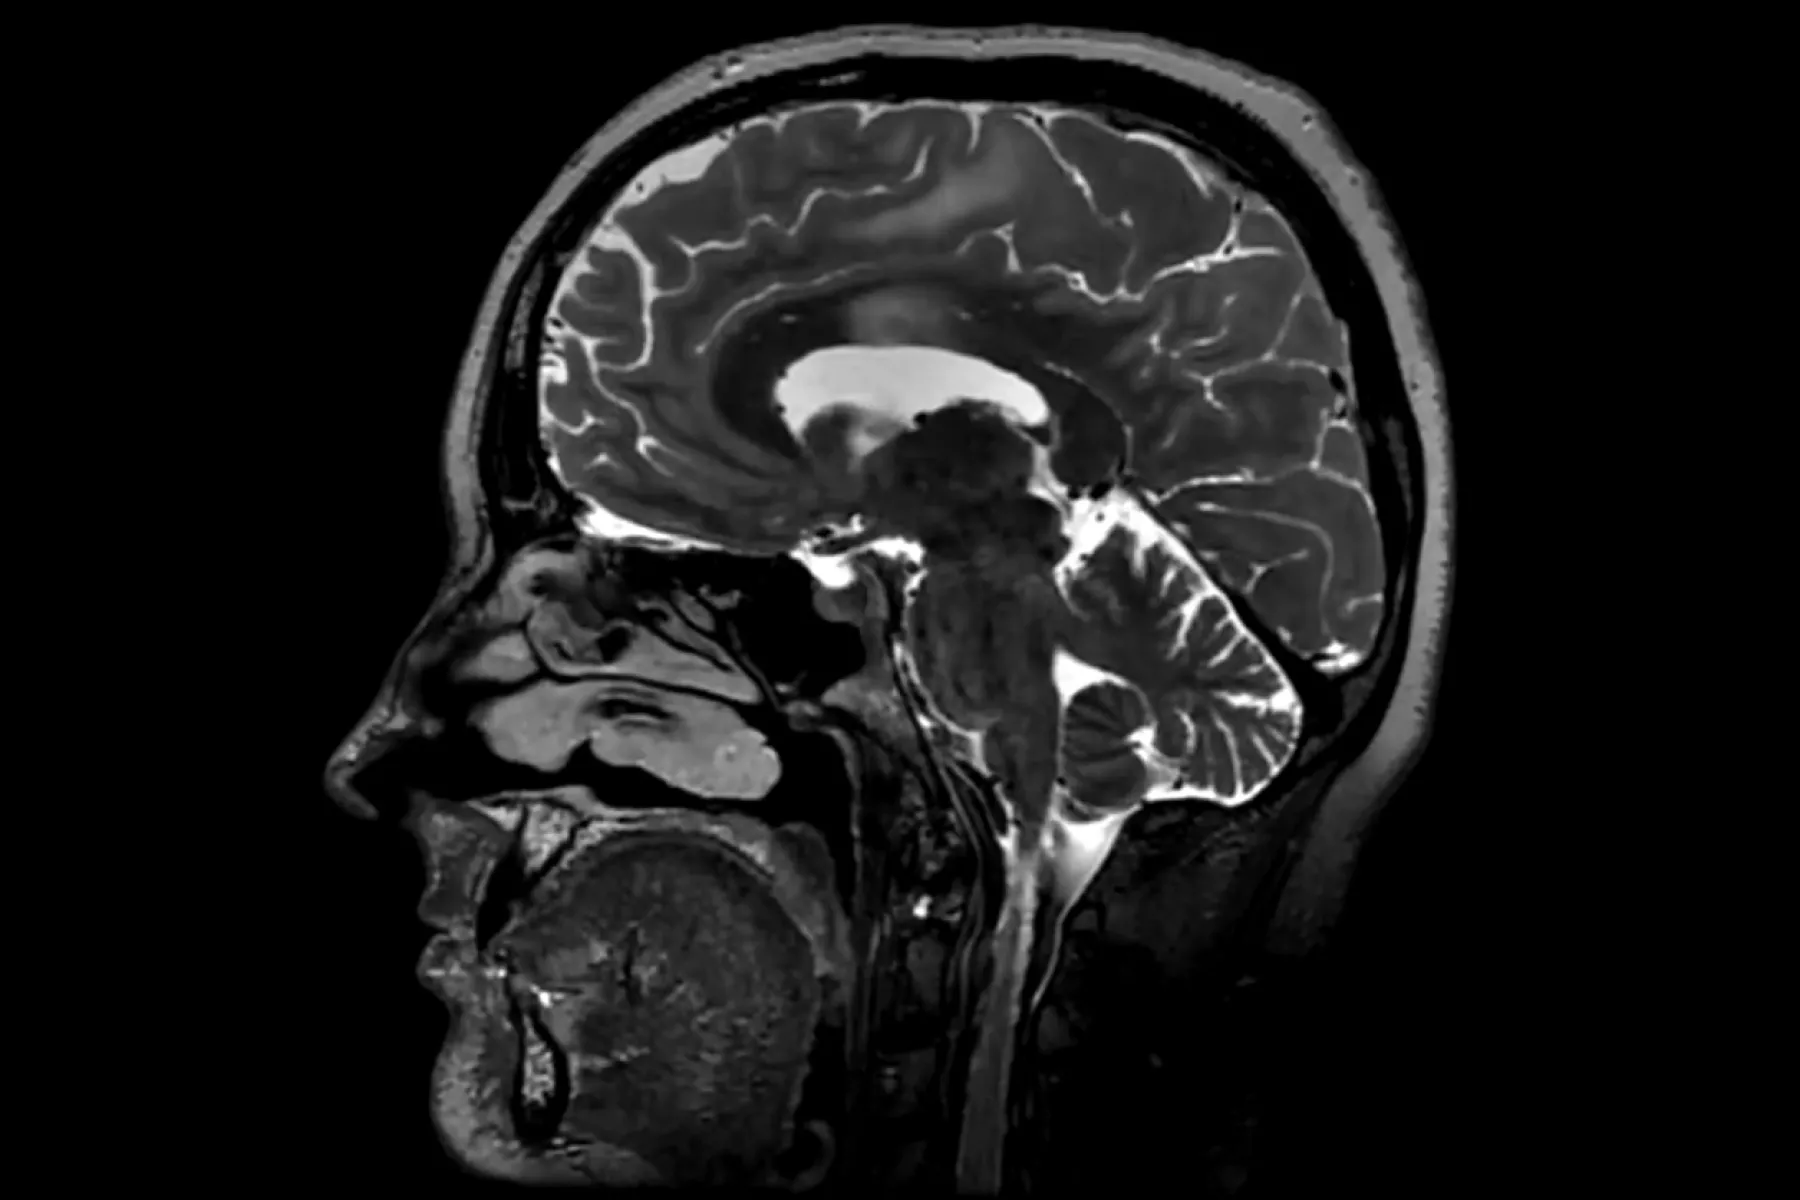

Universidad de Cambridge postula que la adolescencia puede llegar a los 30 años

El estudio "Puntos de inflexión topológicos a lo largo de la vida humana" (Topological turning points across the human lifespan) fue publicado en la revista Natura Communications el 25 de noviembre de 2025. (gorodenkoff/Getty Images)